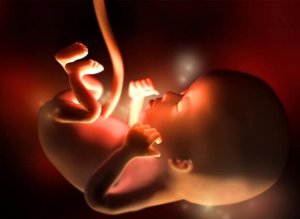

Gebeliğin 12. haftası, bebeğin boyunun 5 ile 6 santimetre, ağırlığının 8 ile 14 gram arasında olduğu ilk trimesterin sonudur. Kalbi çok güçlü -dakika başına 160 kere – atar ve hareketleri hala hissedilemese de, çoğalmaya başlar.

Gebeliğin bu döneminde, bebeğinizin boyutu, bir erik ya da çarkıfelek meyvesi kadardır. Aslında, geçen hafta ve bulunduğunuz hafta arasında, bebek yaklaşık %15 büyür. Uzuvları zaten oluşmuştur, organlar hızlıca olgunlaşmaya başlar ve hatta şu anda göbek bağının tabanına kadar olan bağırsaklar, karın boşluğuna taşınmaya başlar.

Kafa, benzer şekilde, yuvarlak bir şekil alır. Ağız açılıp kapanabilir ve kulaklar olmaları gereken yerdedir. Tırnaklar ve ses telleri oluşmaya başlar. Gebeliğin 12. haftasında, böbrekler küçük miktarlarda idrar üretmeye başlar ve hatta vücutta ilk saç belirtileri görünür.

Cinsiyet henüz ultrason ile belirlenememesine rağmen, bu aşamada cinsel organ tam gelişim halindedir. Bu süre içinde bebek esneyebilir, hıçkırabilir ve yutkunabilir. Şimdi, çocuğumuzun geliştiğini gördüğümüz bu dönemde, doğanın harikaları belirmeye başlar.